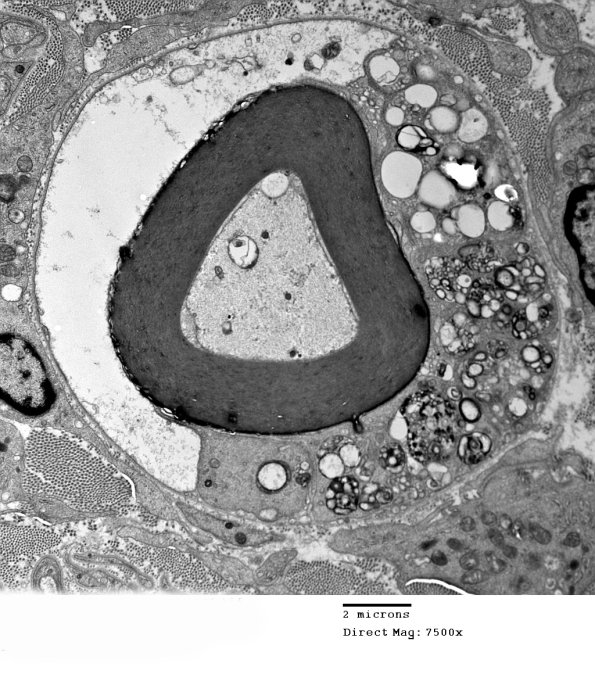

1D6A,B The Schwann cell cytoplasm is again pale without degenerating myelin droplets; there are several macrophage processes containing myelin fragments. (electron micrographs)